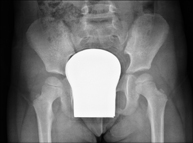

Procediment que permet, mitjançant l'ús de raigs X, i després d'injectar un contrast a l'interior de l'articulació, detectar lesions d'aquestes articulacions (cartílag, os, tendons, etc. ) segons la distribució del contrast. - RX Pelvis

Procediment que usa els raigs X a través de la qual s'obtenen imatges de la pelvis per al seu estudi, especialment dels ossos pèlvics. - RX Edat òssia

Estudi que usa els raigs X a través de la qual s'obtenen imatges del maluc i permet descartar luxacions. - RX Seriada òssia